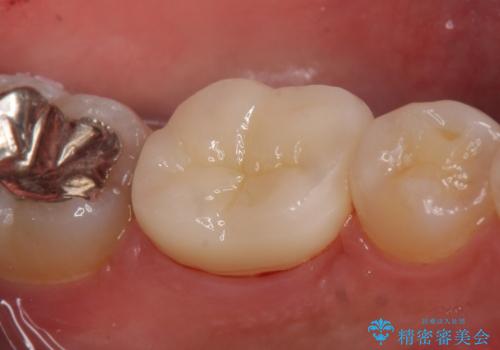

- 左下6の咬耗により歯がしみるている方の症例です。

オールセラミッククラウンによる補綴を行い、症状はなくなりました。

今回用いたオールセラミッククラウンは、ジルコニアフレームという白い素材の上にセラミックを盛っているため審美性が非常に高いのが特徴です。

またジルコニアは人工ダイヤモンドの材料にも使われているほど高い強度を持っており、そのためオールセラミッククラウンは審美性だけでなく、奥歯やブリッジの補綴も可能とするクラウンです。